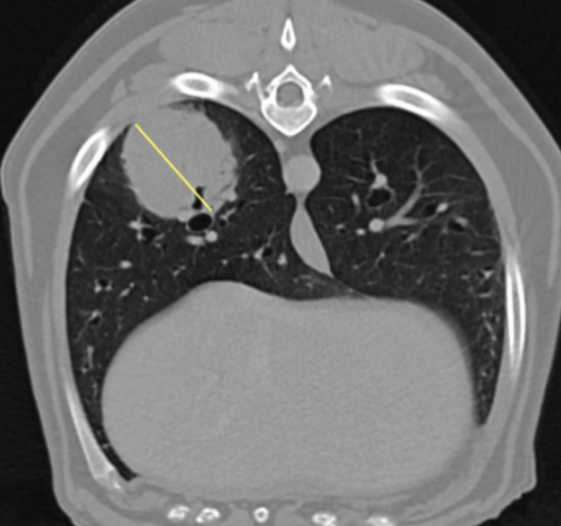

The pre-contrast images of the thorax showed a large bronchocentric mass in the right caudal lung lobe, with irregular contours (Image 5). There was one further smaller nodule in the periphery of the right caudal lung (Image 6). The cardiovascular, mediastinum and trachea all appeared normal.

Image 5: Large nodule in the right caudal lung lobe (yellow line indicates width).